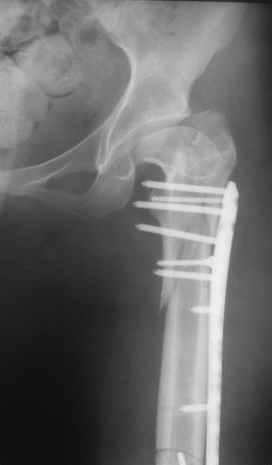

Уважаемые коллеги, приношу извенения за молчание. Готовили материал и боялись писать раньше времени. Все хотели убедиться в том, что после операции все будет спокойно. Спасибо за отклики и советы. К сожалению, гамма-гвоздя, штифтов с возможностью установки более 2-х блокирующих винтов у нас нет. Зато нашли достаточно длинную пластину с угловой стабильностью. После проведения предоперационной подготовки и планирования выполнили остеосинтез. В условиях рентгеноперационной, после репозиции дистрактором из одного разреза 5см в проксимальном отделе подкожно установили пластину. Пришлось выполнить дополнительный разрез до5см в проекции перелома диафиза в средней трети, из которого удалось репонировать перелом и выполнить фиксацию стягивающим винтом. Затем все завершилось наложением пластины с угловой стабильностью. Пластина оказалась достаточно длинной, что позволило перекрыть все переломы с фиксацией каждого отломка минимум 5-ю винтами. Синтез достаточно стабилен. Пациентка активизирована на 3-и сутки(снимки прилагаются). В настоящий момент пациентка выписана на амбулаторное лечение. Еще раз, огромное спасибо всем за помощь в выборе тактики и просто совете. С уважением Украинский Е.

Прошу прощения, со снимками глюк произошел. Высылаю. С уважением Евгений У.

Получилось очень симпатично, мои поздравления. А можно фото конечности без наклеек посмотреть?